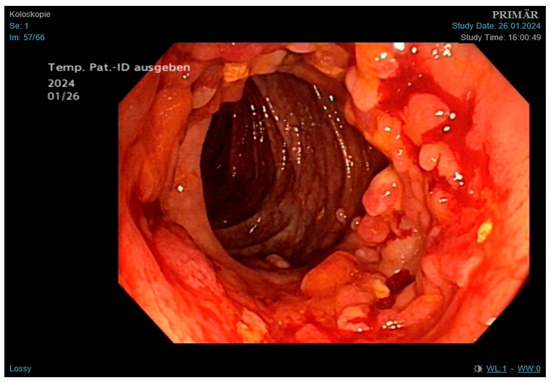

Outpatient chest X-ray showed findings suggestive of pulmonary infection. Laboratory results revealed microcytic anemia with suspected iron deficiency. Sputum microscopy and PCR confirmed Mycobacterium tuberculosis. Given the patient’s abdominal pain and a finding of melena in a setting of known CD, colonoscopy was performed. During the procedure, we saw numerous pseudopolyps and fibrin-coated ulcerations (Figure 4) in the cecum and colon ascendens et transversum, which are consistent with both CD and GI TB. Histopathology showed severe ulcerative and granulomatous inflammation (Figure 5) but was not able to distinguish between the two conditions. Only after subsequent PCR testing demonstrated M. tuberculosis DNA did we confirm that the active infection had caused this severe form of colitis.

In the second case, the patient presented with imaging findings suggestive of primary TB. Both smear microscopy and PCR testing were positive, allowing for early treatment. The primary diagnostic challenge, however, was distinguishing GI TB from a CD flare. Due to overlapping features, misdiagnosis is common: up to 20% of CD patients are misdiagnosed with TB, and 10% of GI TB cases are mistaken for CD [35]. In this patient, constitutional symptoms such as malaise and weight loss favored TB, while melena pointed toward CD [9]. Histopathologic similarities in both conditions add further difficulty. During the colonoscopy, we observed multiple pseudopolyps, which can occur in both diseases. We also saw small circular ulcerations, which are more characteristic of GI TB [36]. Microscopy showed transmural inflammation and epithelioid histiocytes, also typical of both conditions. The subsequent PCR testing, however, confirmed active GI TB. This once again underlines the importance of this test in similar clinical scenarios.

Figure 4. Findings obtained during colonoscopy, showing multiple pseudopolyps and fibrin-coated ulcerations; findings consistent with both Crohn’s disease and GI tuberculosis.